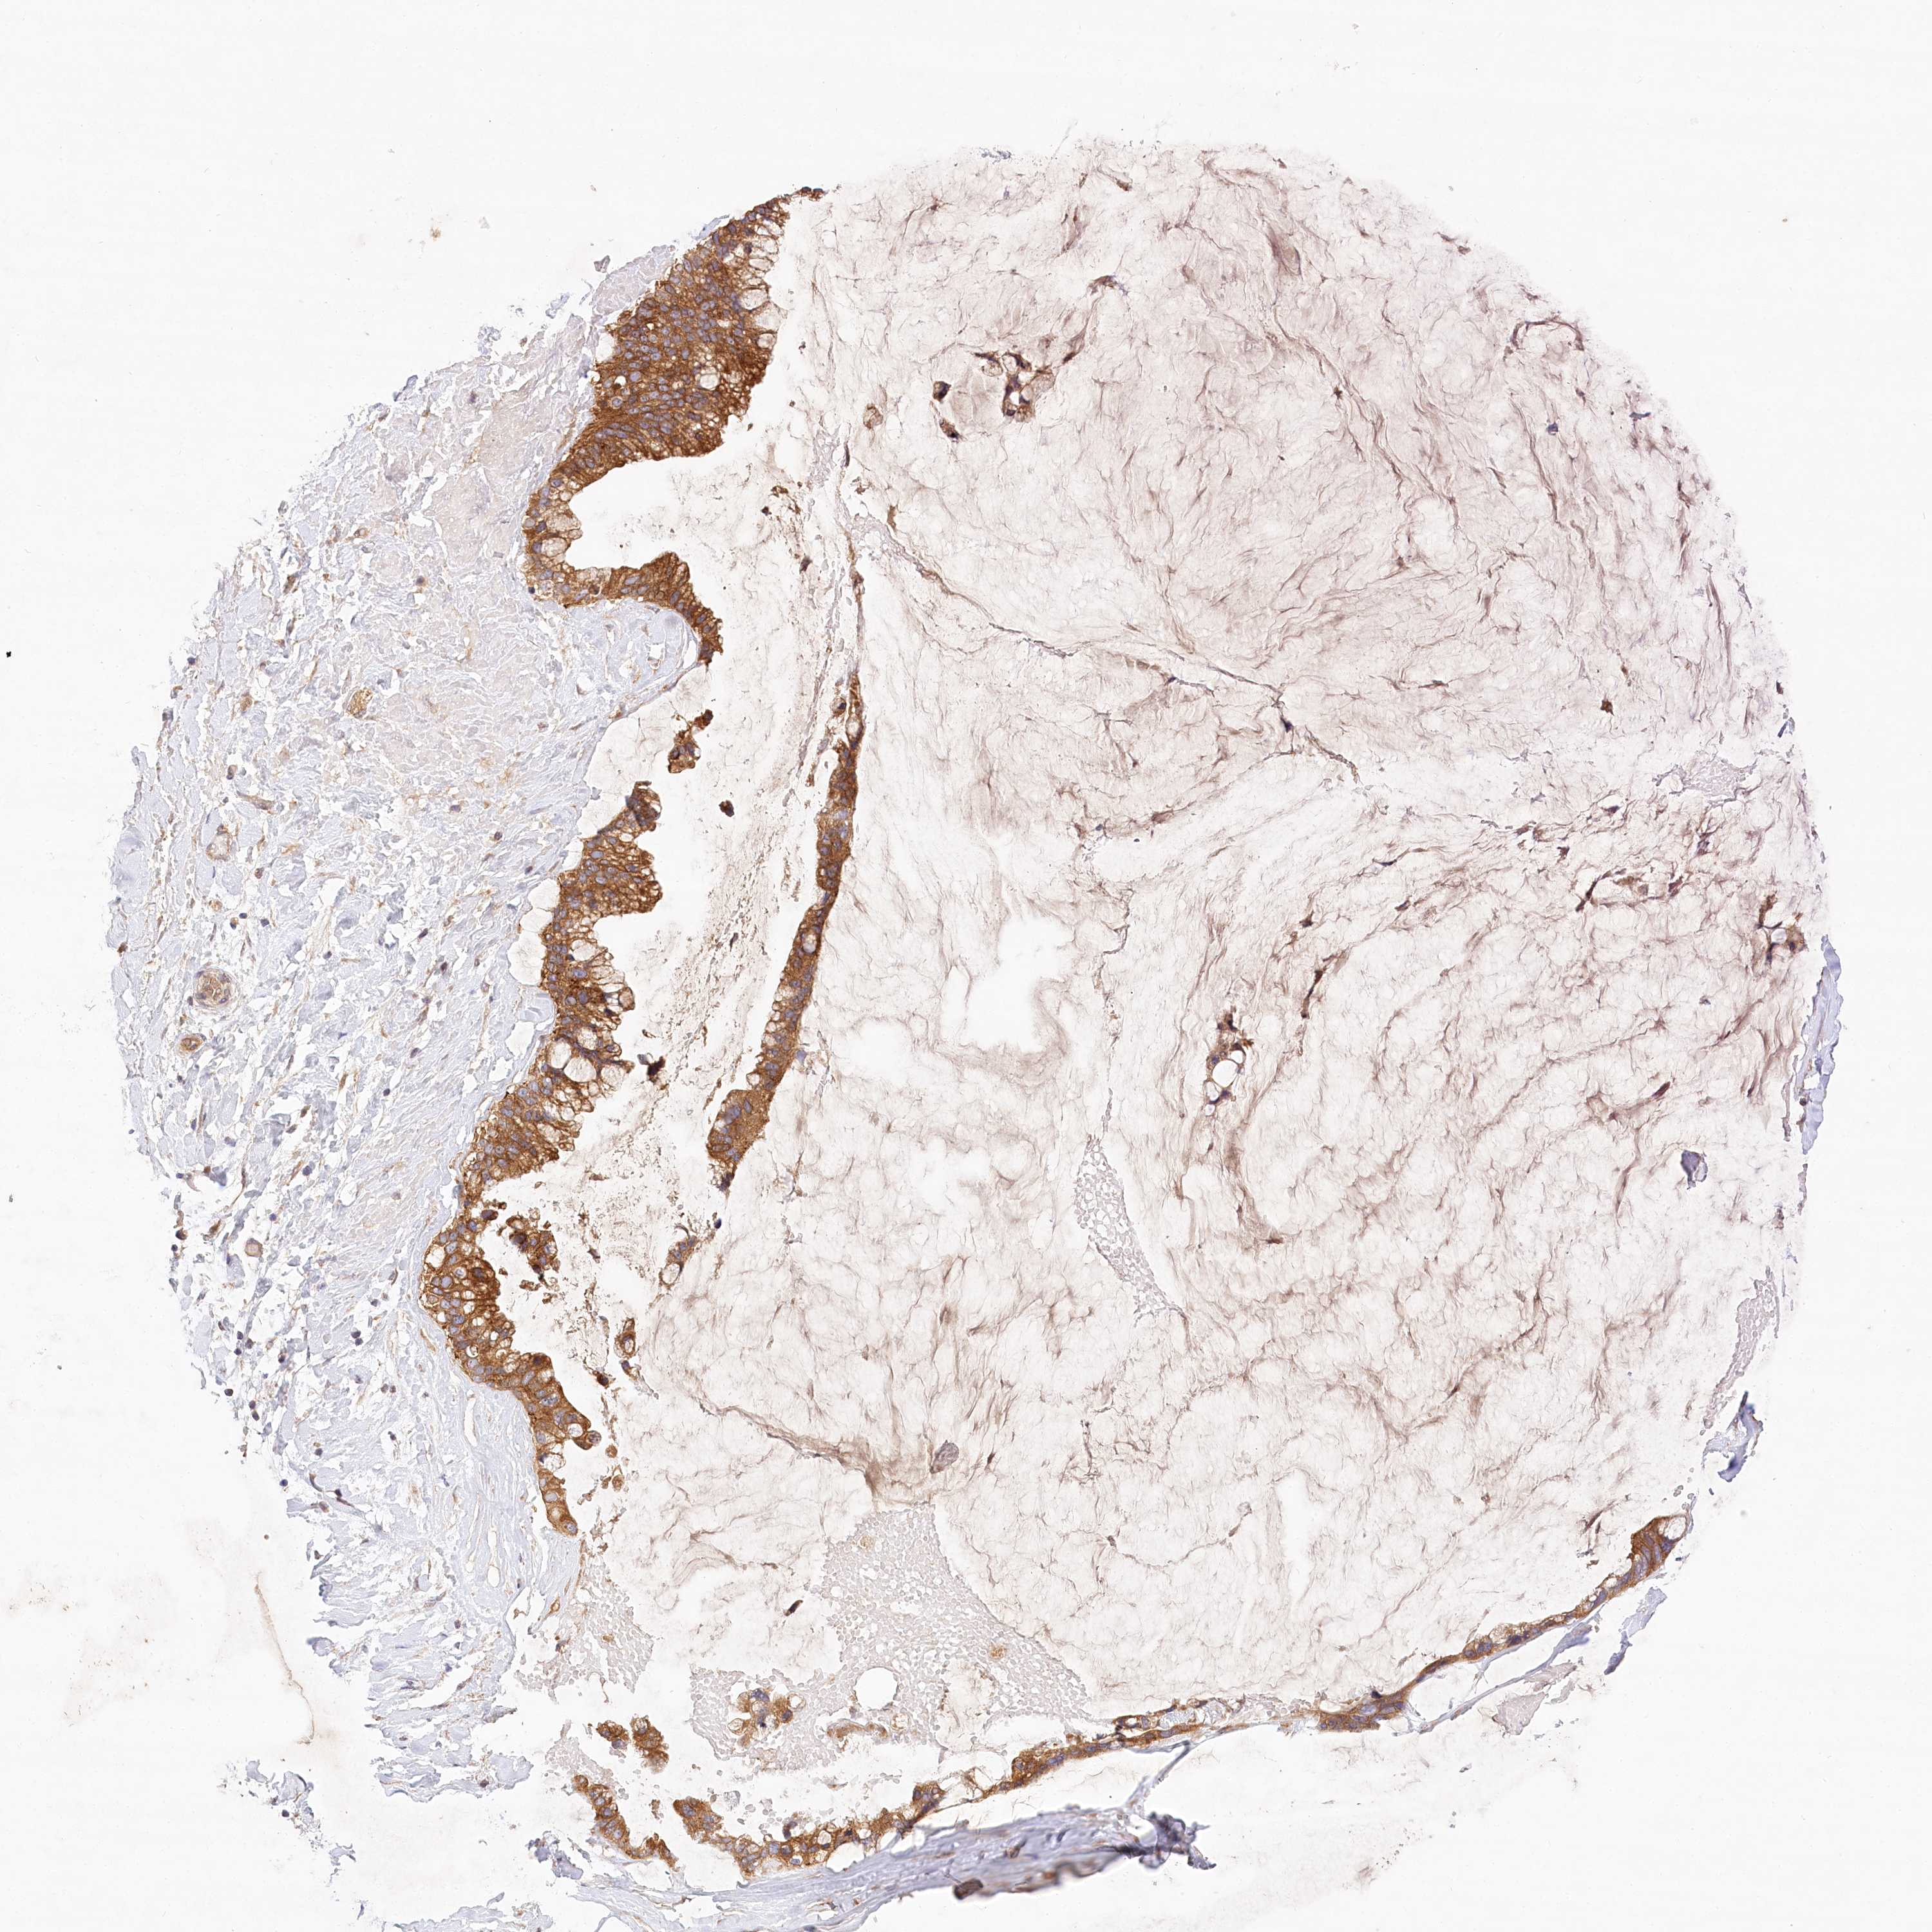

OVARIAN CANCER - Protein expressioni

A mouse-over function shows sample information and annotation data. Click on an image to view it in a full screen mode. Samples can be filtered based on level of antibody staining by selecting one or several of the following categories: high, medium, low and not detected. The assay and annotation is described here.

Note that samples used for immunohistochemistry by the Human Protein Atlas do not correspond to samples in the TCGA dataset.

Antibody stainingi

Antibody staining in the annotated cell types in the current human tissue is reported as not detected, low, medium, or high, based on conventional immunohistochemistry profiling in selected tissues. This score is based on the combination of the staining intensity and fraction of stained cells.

Each image is clickable and will lead to virtual microscopy that enables deeper exploration of all samples and also displays staining intensity scores, fraction scores and subcellular localization as well as patient and tissue information for each sample.

Antibody HPA032060

Antibody HPA032062

Antibody CAB034116

Staining

High

Medium

Low

Not detected

Cystadenocarcinoma, serous, NOS

Carcinoma, endometroid

Cystadenocarcinoma, mucinous, NOS

Carcinoma, NOS